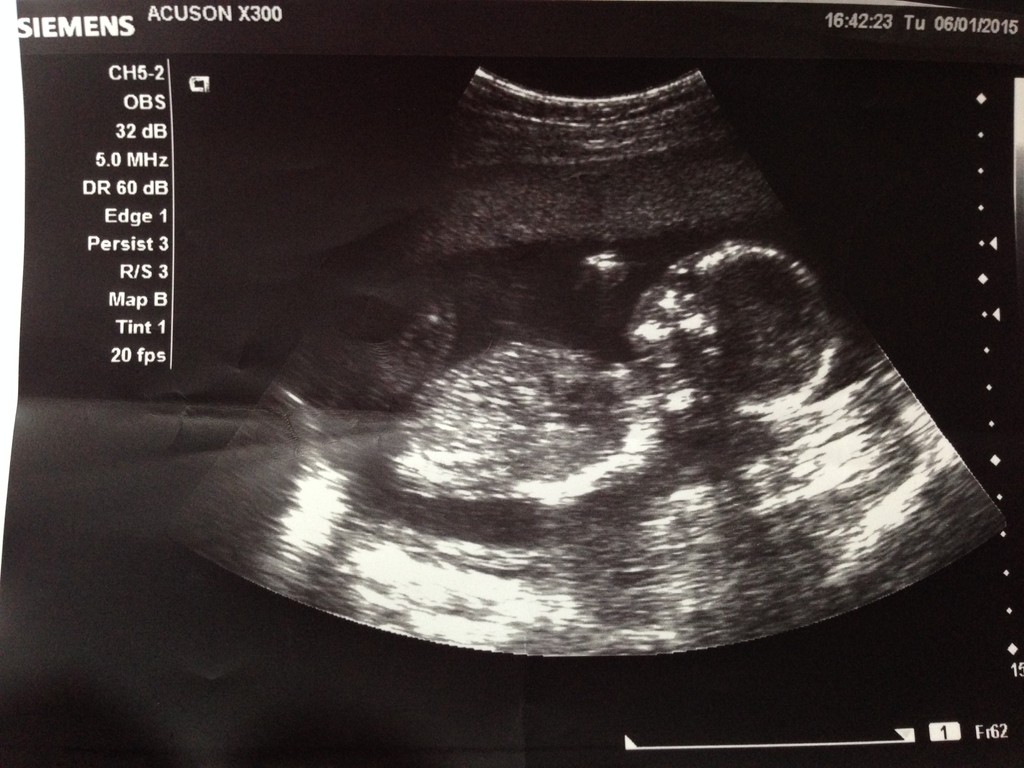

【17W3D蹦蹦骨:3.93cm,咪重:53kg】

的蹦蹦: